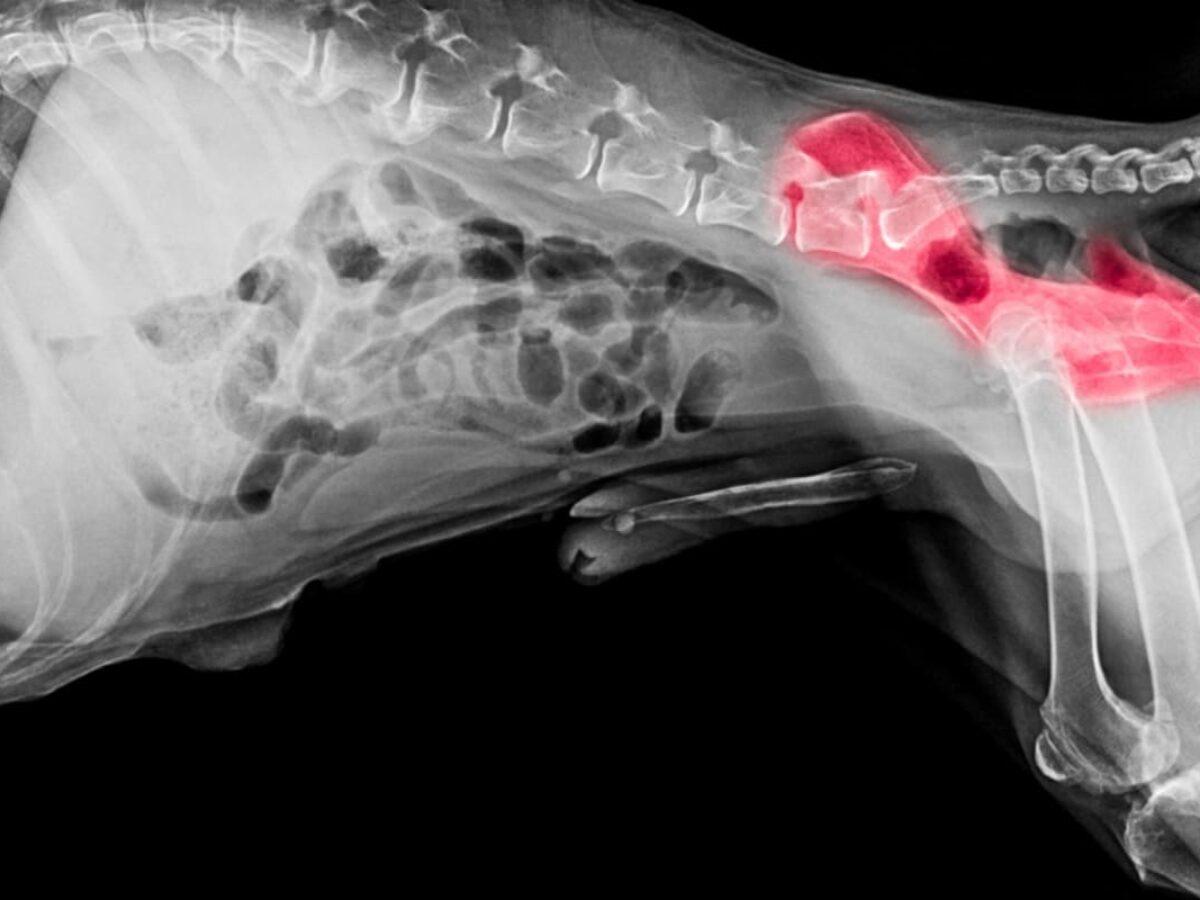

Decalcifierea osoasă se referă la pierderea progresivă a densității minerale și a integrității structurale a osului, ceea ce poate crește fragilitatea și susceptibilitatea la fracturi. Cauzele sunt multifactoriale și pot include modificări hormonale, aport nutrițional insuficient, sedentarism, afecțiuni cronice și utilizarea unor medicamente; fiecare factor poate contribui diferit în funcție de contextul individual.

În practică, pierderea de substanță osoasă poate fi silențioasă până la apariția unei fracturi sau a durerii; de aceea evaluarea se bazează pe investigații imagistice și examinare clinică efectuate de un specialist. Măsurile de gestionare includ intervenții asupra stilului de viață și suport nutrițional care pot ajuta la menținerea sănătății osoase și strategii medicale personalizate care pot susține reducerea riscului; pentru informații suplimentare, consultați resursele relevante. Atenție: discutați cu un medic sau cu un specialist înainte de a începe orice intervenție.

Evaluarea inițială se bazează pe o anamneză detaliată și examinare fizică pentru a identifica factorii de risc care pot contribui la decalcifiere osoasă, precum istoricul de fracturi, schimbările hormonale, medicația sau afecțiuni cronice. Simptomele pot include durere osoasă, pierdere în înălțime sau fracturi la traumatisme minore, însă uneori modificările de densitate osoasă pot fi asimptomatice; o evaluare clinică completă poate ajuta la stabilirea necesității investigațiilor suplimentare.

Investigațiile pot include metode imagistice pentru evaluarea densității și a eventualelor fracturi, iar analizele de sânge pot contribui la identificarea unor cauze secundare sau a factorilor metabolici care influențează sănătatea osoasă. În funcție de rezultate, poate fi utilă o discuție cu un specialist pentru a decide pașii următori și pentru a stabili un plan de monitorizare individualizat.